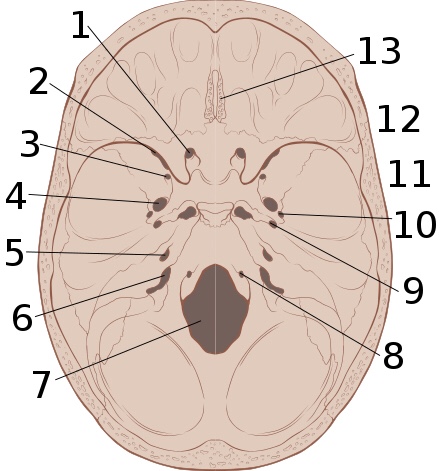

<img alt=”” src=”//upload.wikimedia.org/wikipedia/commons/thumb/8/84/Skull_interior_anatomy.svg/220px-Skull_interior_anatomy.svg.png” decoding=”async” width=”220″ height=”235″ class=”thumbimage” data-file-width=”470″ data-file-height=”503″>

The interior of the skull has sharp ridges by which a moving brain can be injured.

Epidural hematoma commonly results from a blow to the side of the head. The pterion region, which overlies the middle meningeal artery, is relatively weak and prone to injury.[10] Thus, only 20 to 30% of epidural hematomas occur outside the region of the temporal bone.[11] The brain may be injured by prominences on the inside of the skull as it scrapes past them. Epidural hematoma is usually found on the same side of the brain that was impacted by the blow, but on very rare occasions it can be due to a contrecoup injury.[12]